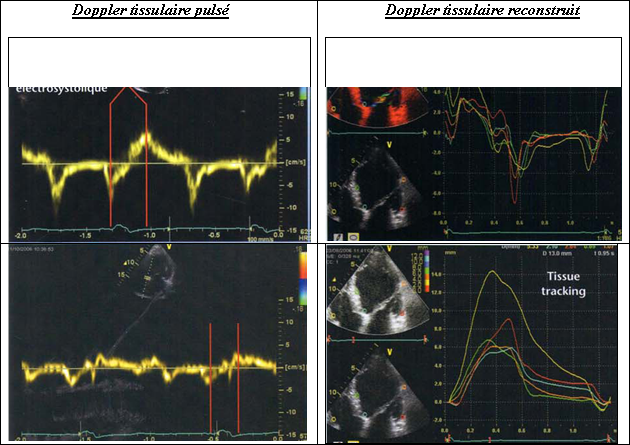

Hình 9: Đo lường những sự lệch thời gian điện - cơ học bằng Doppler tissulaire pulsé

Hình 10: Đo lường những sự lệch thời gian điện - cơ học bằng Doppler tissulaire pulsé hoặc tái tạo. Tissue tracking: kiểu dịch chuyển.